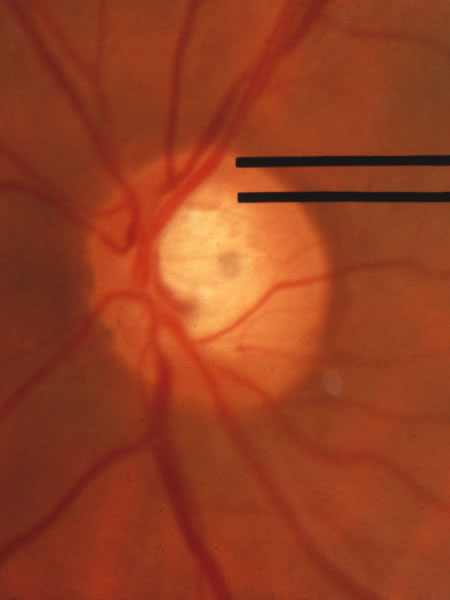

The approximately 1 to 1.5 million axons that form the optic nerve arise from the retinal ganglion cells and course toward the optic disc in a well-known pattern (Fig. 1). From the nasal retina the fibers take a straight course toward the disc. Axons originating temporal to the fovea arc around the macula to enter the upper and lower poles of the optic nerve head. The macula fibers pass directly to the temporal quadrant of the disc in the papillomacular bundle.

Fig. 1. Fundus photograph shows the normal pattern of the retinal nerve fiber layer. (Courtesy of P. Juhani Airaksinen, MD).